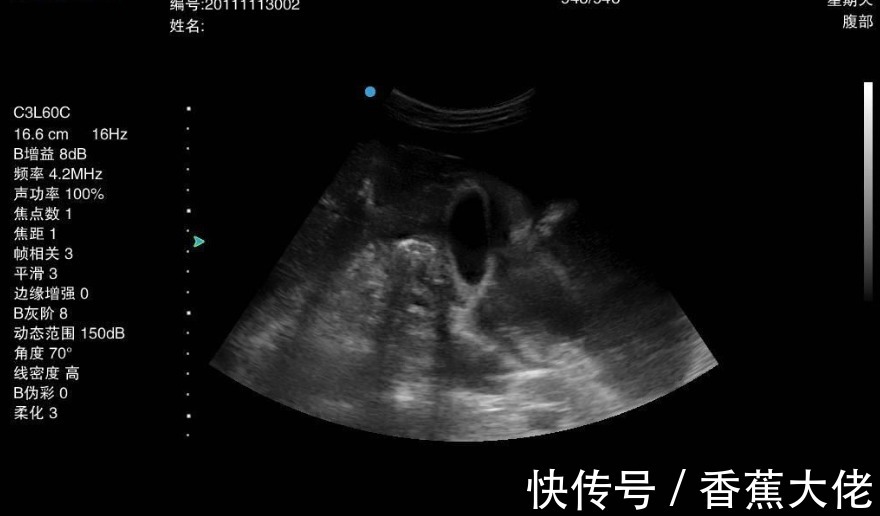

到医院后,医生建议他做一个胃镜检查,这一检查才知道,小金得了胃癌,小金很疑惑:近年来饮食上都很清淡,没有乱吃什么,就是有一个单纯的胃炎病,怎么还变成胃癌了呢?